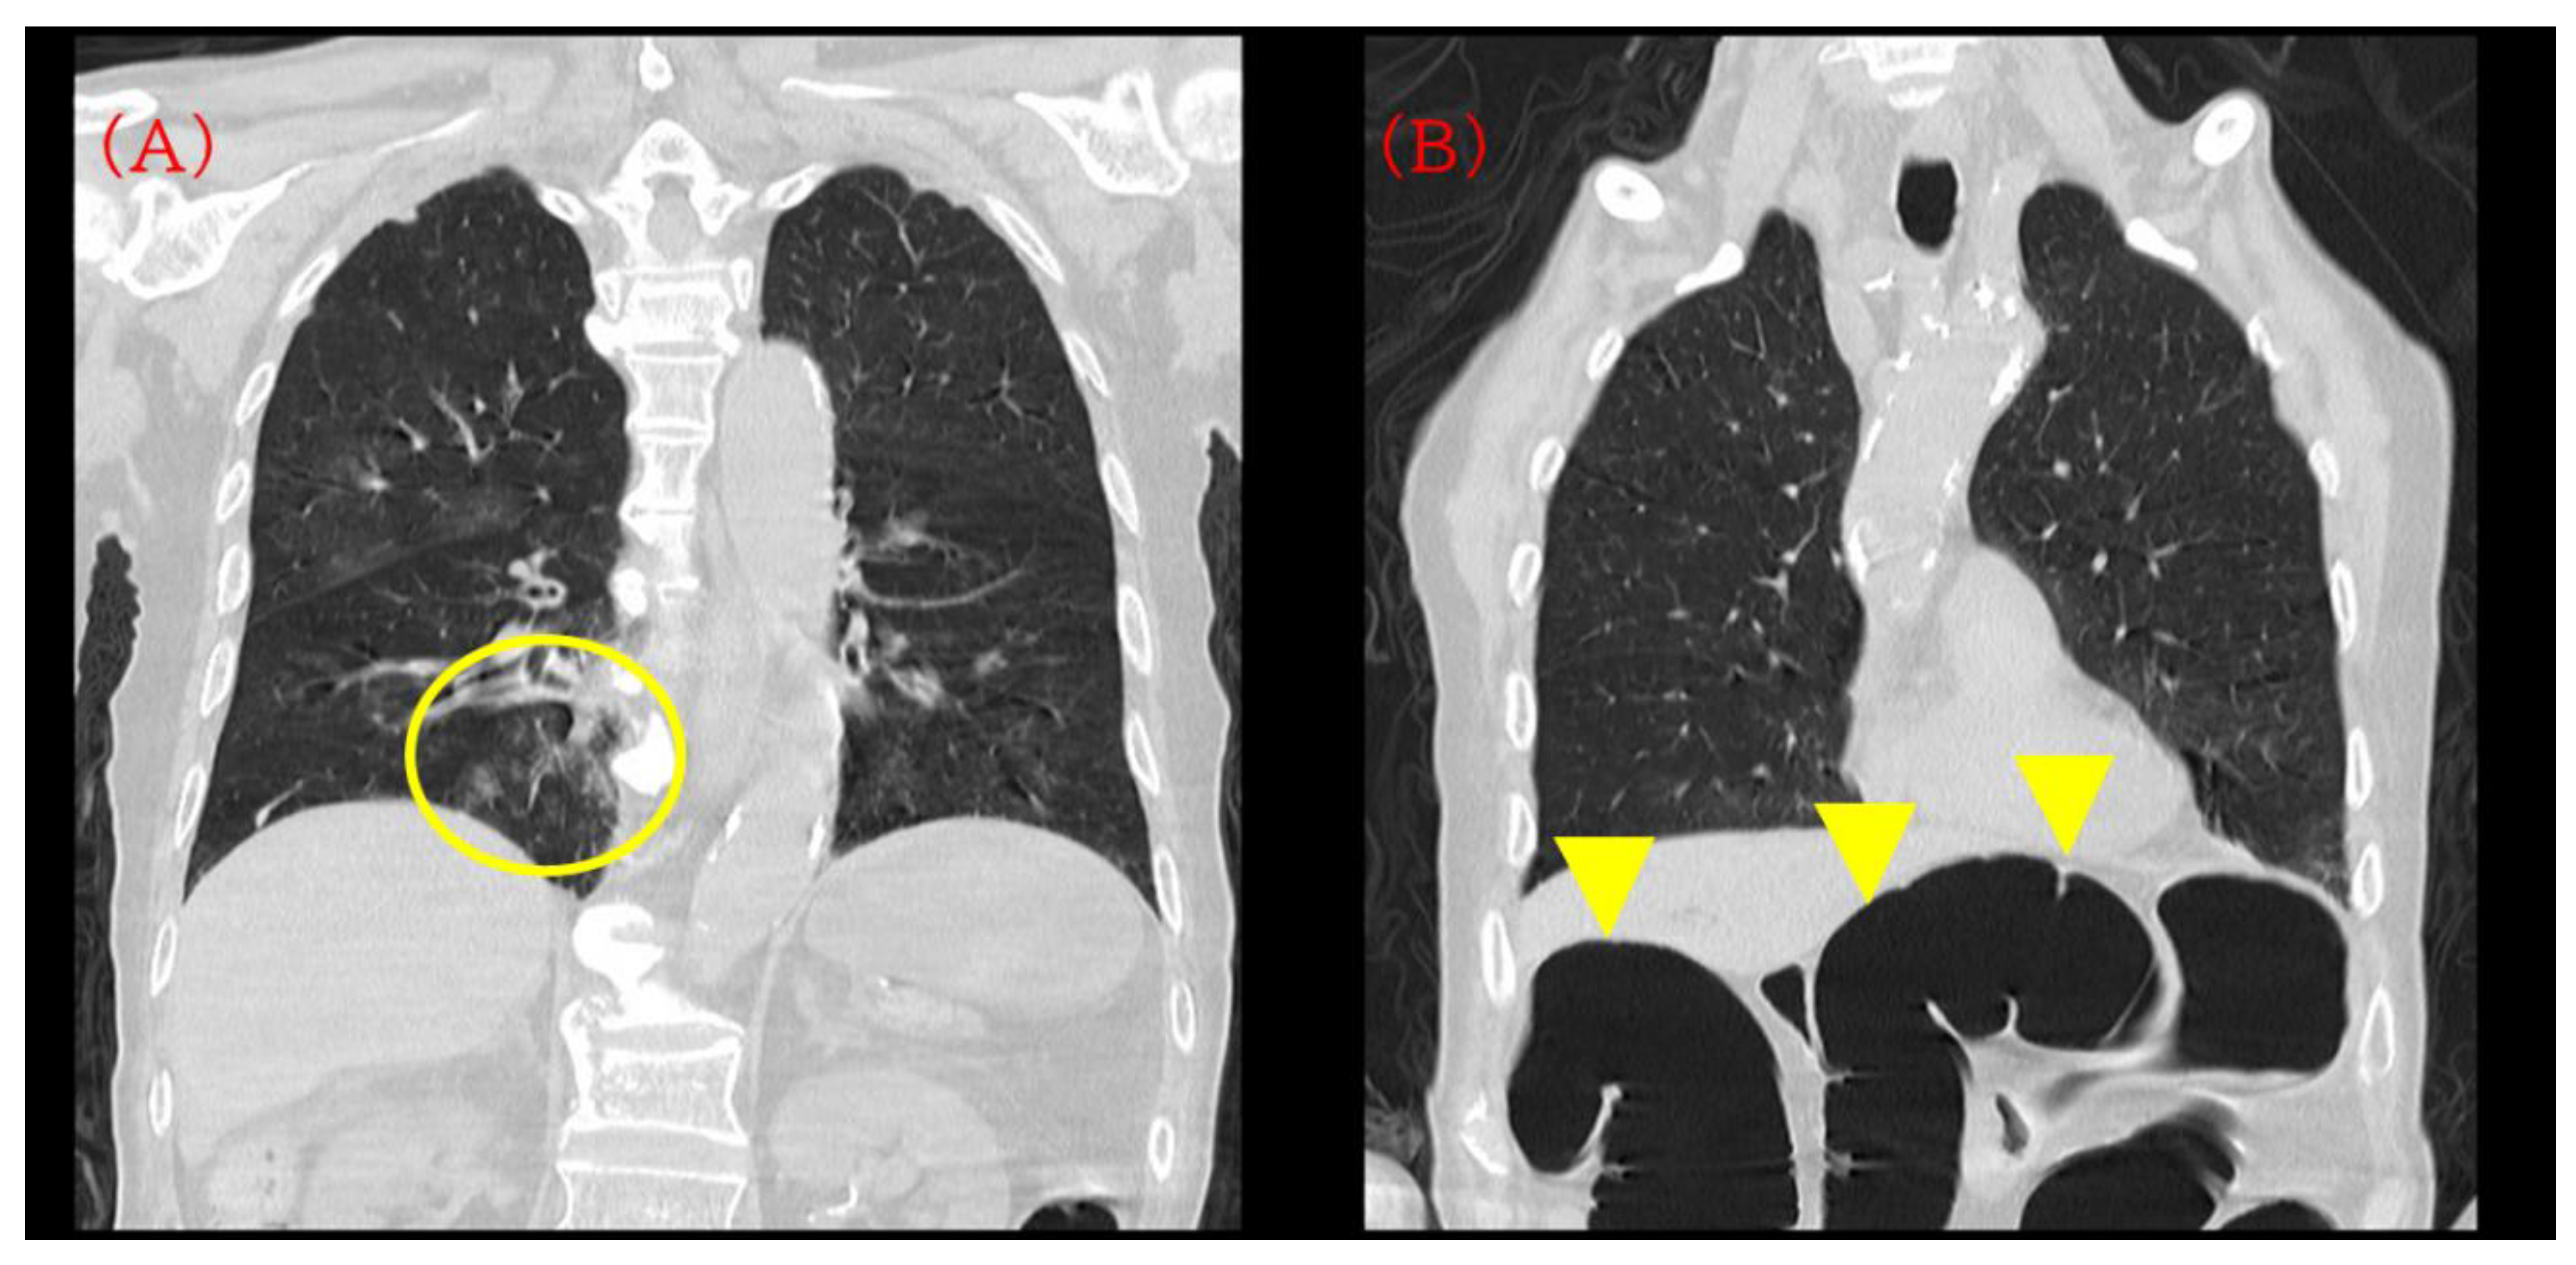

Chest CT showed mild bronchopneumonia predominantly in the right lower lobe without extensive consolidation or large pleural effusions (Figure 1A). On the same CT series, a moderately distended transverse colon with intraluminal gas was incidentally visualized within the scan range, suggesting pre-existing colonic dilatation at admission (Figure 1B). Non-contrast head CT confirmed bilateral CSDHs, more prominent on the right, compressing both cerebral hemispheres (Figure 2A).

Figure 1.

Initial computed tomography (CT) on admission. (A) Chest CT demonstrating mild bronchopneumonia predominantly in the right lower lobe without extensive consolidation or pleural effusion (yellow circle). (B) The same CT series incidentally showing a moderately distended transverse colon with intraluminal gas (yellow arrowhead). This finding was visible on the admission CT but was not pursued with dedicated abdominal evaluation at that time and was later revisited during case review.